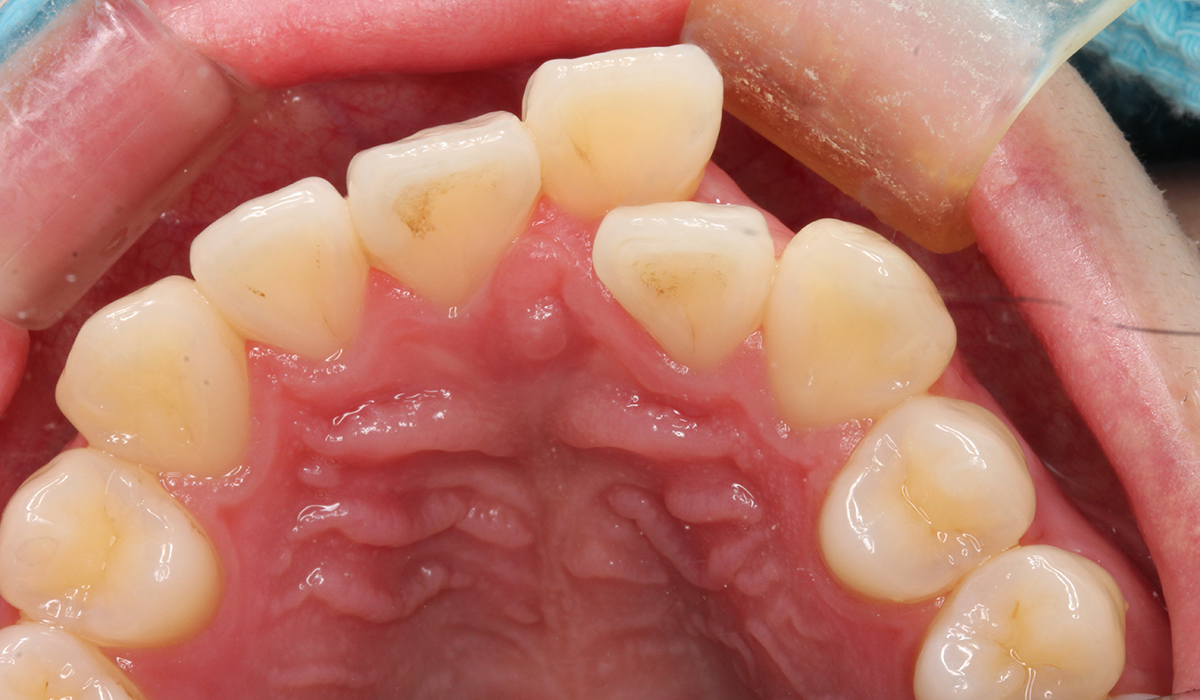

上顎

術前